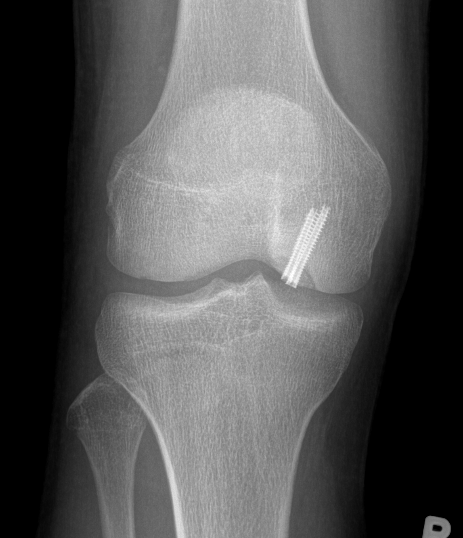

Medial femoral condyle

Technique

Arthroscope in lateral portal

Clear fat pad

Ensure can see entire dimensions of OCD

If fragment is displaced, reduce and pin with accessory K wire

Instrument and screw from accessory medial portal

- fragment is lateral aspect of the MFC

- typically need trans patella tendon portal to ensure correct trajectory

- ensure K wires centered in fragment

Flex and extend knee to place inferior / superior screws

- typically 2 - 3 screws maximum (3.5 mm)

- 22 - 26 mm long, want to stop short of growth plate

- ensure screw heads are buried under cartilage, but not too deep so they still engage fragment

- can microfracture with 1 mm k wire around screws